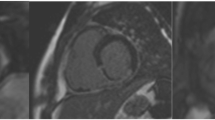

Hyperintense myocardial segments were present in all subjects on STIR images acutely and corresponded to the vascular territory downstream of the occluded coronary artery at angiography (Figure 2). At the acute stage, the per-segment sensitivity and specificity of STIR on visual assessment to detect infarcted segments was 95% and 78% respectively, and on semi-quantitative assessment was 99% and 83% respectively.

Matched diastolic STIR and LGE images obtained in 5 patients post MI (A = acute STIR, B = acute LGE, C = 6-month STIR, D = 6-month LGE). Transmural edema can be seen in all acute STIR images, which disappears by 6-months. Hyperintense areas with central hypointensity on acute STIR imaging are seen in the first and third patients. These hypointense areas correspond with areas of microvascular obstruction seen on the corresponding LGE images and are thought to represent myocardial hemorrhage.